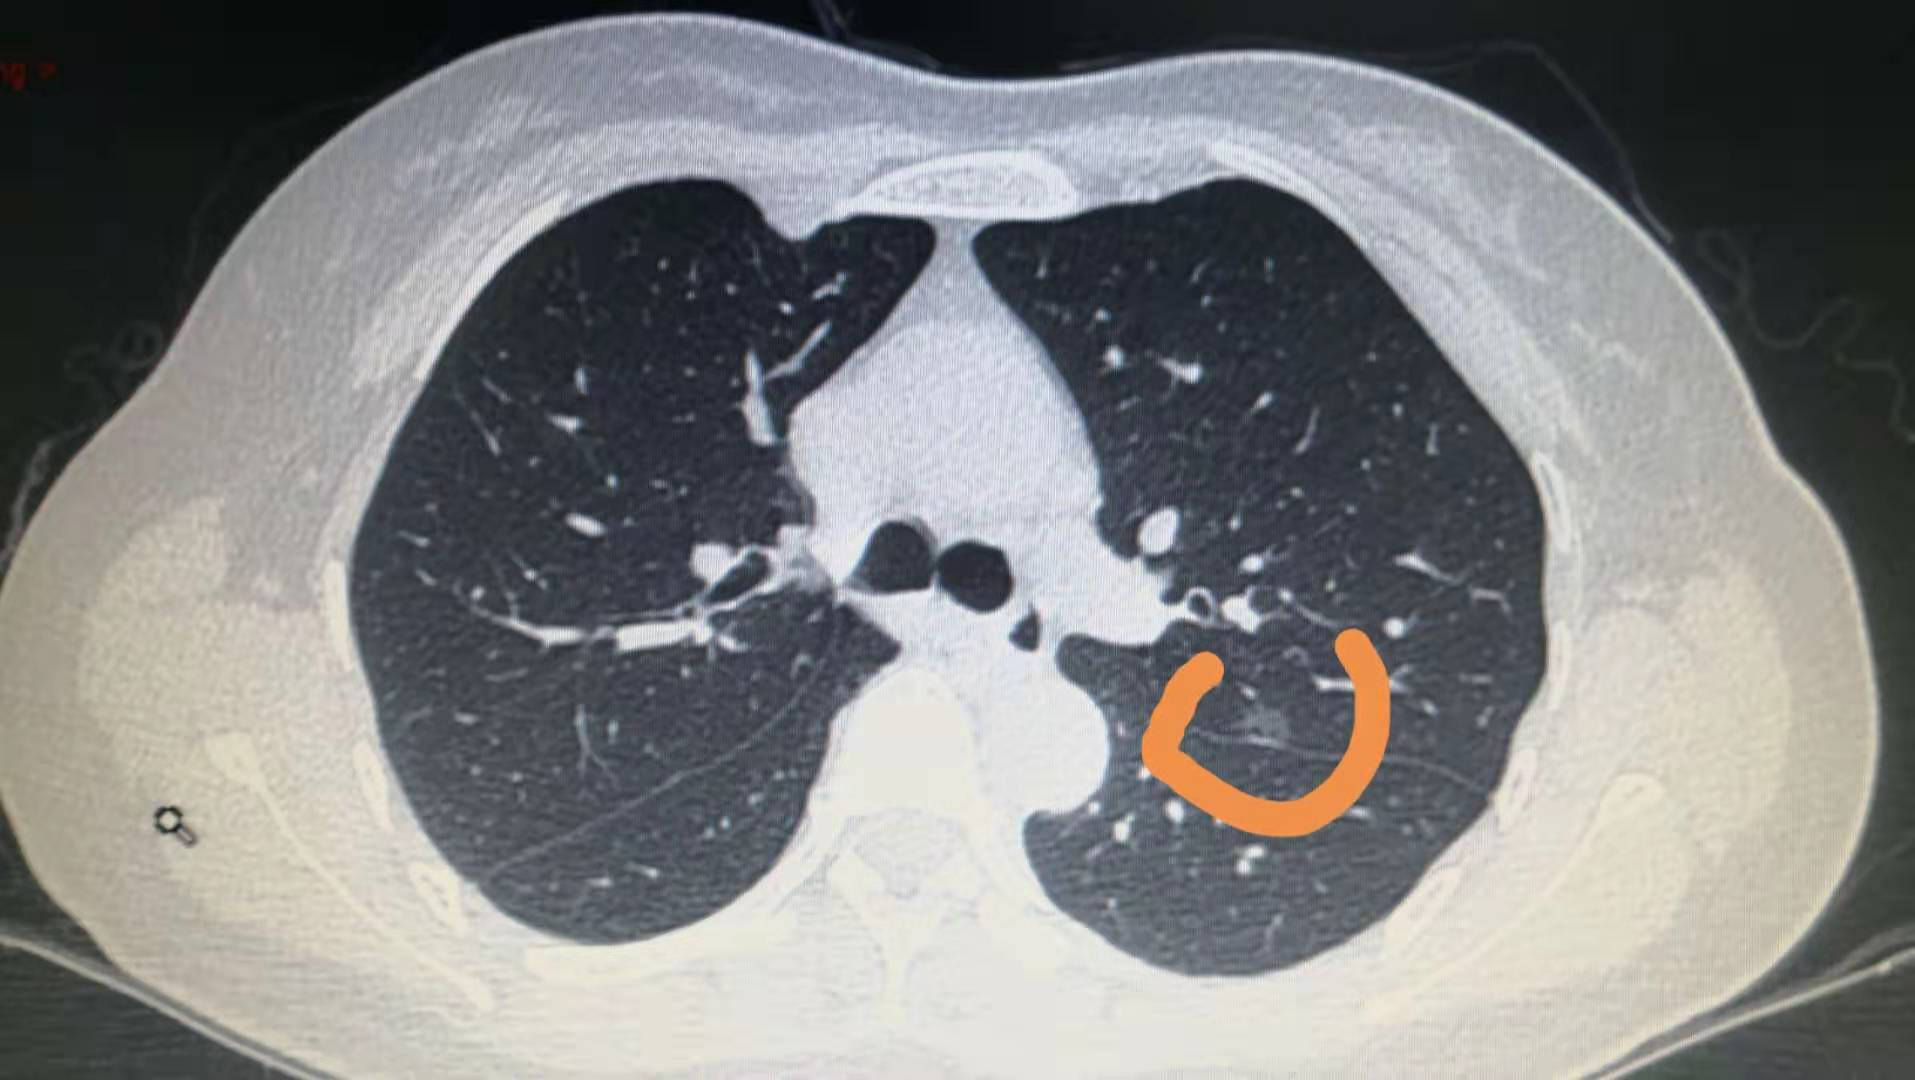

体检发现的肺部小结节,一般是指至今不超多2厘米的小肿块,恶性占5%左右。肺内多种疾病都会形成结节,如炎症、结核、霉菌、亚段肺不张等;在直径大于2.5厘米的肺内单发结节中,恶性占到一半以上。直径超过2厘米的肺部小结节恶变率为64%~82%;

肺部小结节处理的基本原则:

1、小于等于2毫米的结节,95%以上属于良性,只需每年随访。

2、6-8毫米结节,每半年随访,定期随访不会耽误病情。

3、大于8毫米的结节,一般建议手术治疗

4、对于第一次发现的纯磨玻璃结节,不需要做任何的治疗,定期随访,3-6个月复查一次,如果没有变化,1-2年再复查。